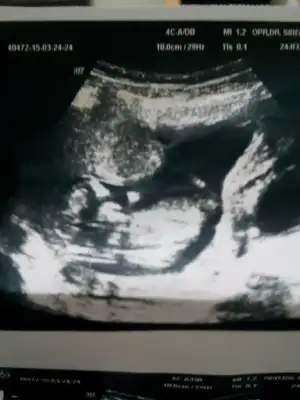

Canim daha kucul ama kiz gibi geldi bama..

Kız zannedersemKizlar banada yorum yapin nolurrr catliyorum merakdannnnn

Buyuj ihtimak kizz...kızlar 14 haftalık hamileyim dr.bişey demedi cinsiyetine lütfen yorumlarmısınız....merakla bekliyoruz......